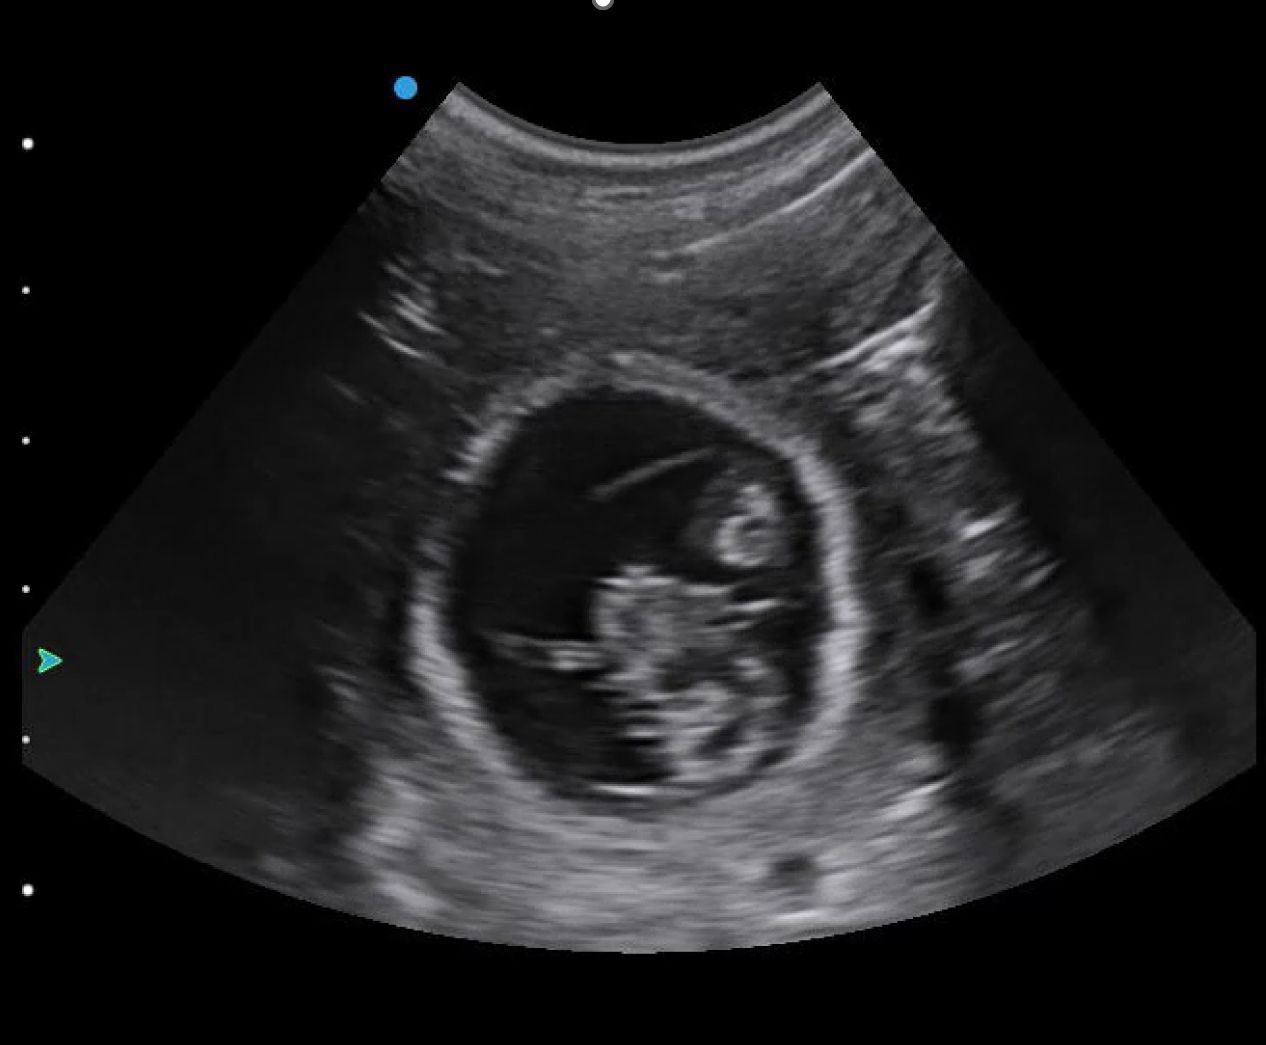

You will likely begin with your depth on its default setting or increased for larger breeds of dog. Once you find a gestation sac (Figure 1), you should optimise your image by reducing your depth and ensuring your focal point is at the level of the foetus. This will allow you to confirm the presence of a heartbeat.

Manipulating your imaging plane is essential for certain measurements, such as crown–rump length and biparietal diameter. Still images can be ambiguous – Figure 3, for example, is not pregnancy – so watching a video clip (Video 1) instead makes this image more interpretable.